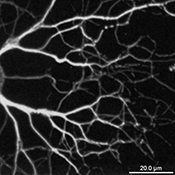

Specimen Image

Original